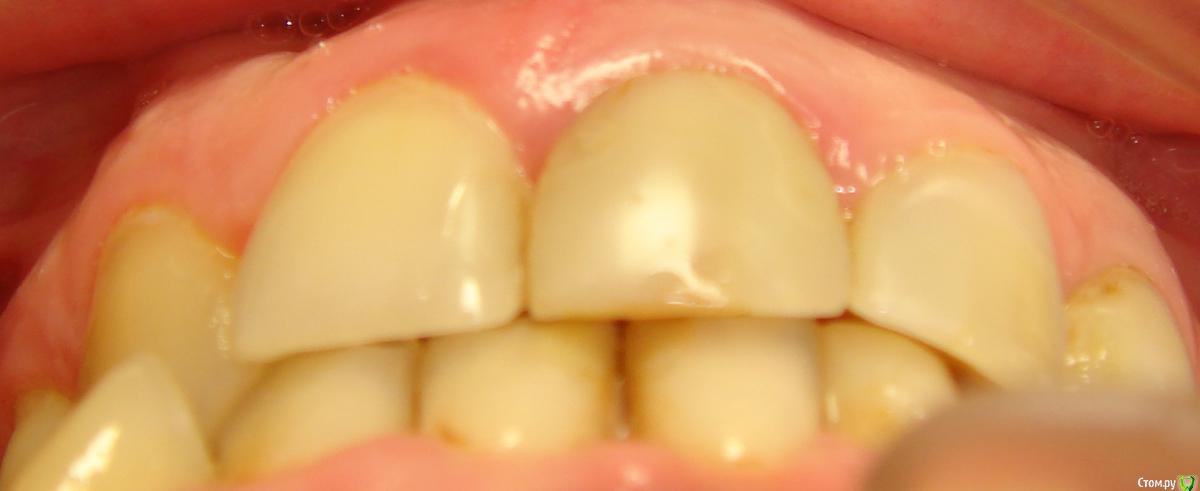

Здравствуйте, Коллеги! Хочу спросить совета по такому случаю. Пациентка 33 года. В детстве удалили 12 зуб, пространство закрыли на съемном аппарате. В подростковом возрасте удалили все остальные отсутствующие зубы. Сейчас носит бюгель. Вопрос такой: заниматься ли мне, как ортодонту формированием полноценного межчелюстного соотношения, или просто решить локальные проблемы и отдать на функциональную реабилитацию ортопеду? И если все-таки заниматься мне, то как??? Лечение такого третьего класса - элементарно для многопетлевой при наличии адекватной опоры, но вот такая адентия заставляет меня сомневаться. Заранее спасибо за ответы!